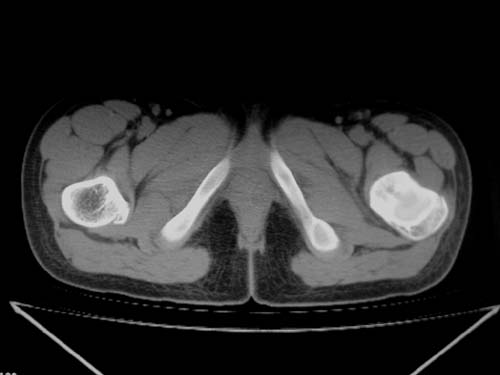

标题: CT19608:女12岁,左髋部疼痛,无发热病史 [打印本页]

标题: CT19608:女12岁,左髋部疼痛,无发热病史

左股骨干增粗,磨玻璃样改变——考虑骨纤维异常增殖症!

考虑左股骨上段骨纤维异常增殖症。

左股骨干增粗,磨玻璃样改变——考虑骨纤维异常增殖症!骨化性纤维瘤?